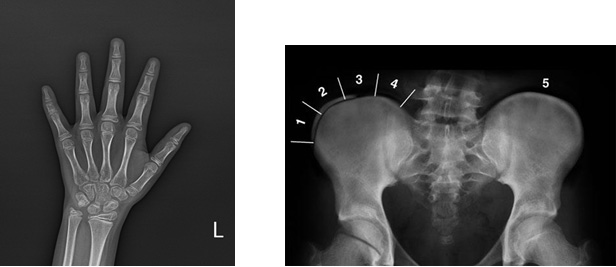

성장호르몬은 성장촉진과 대사에 작용하며 중추신경계 질환, 뇌종양, 외상, 방사선 조사 등에 의해서도 기능저하가 초래될 수 있습니다. 성장호르몬이 결핍되어 유발되는 저신장은 성장 속도가 연 4cm에 미치지 못하며 골연령이 저하되어 있어 호르몬 치료를 하지 않는 경우에 최종 성인 키는 작아지게 됩니다.

조기발견의 중요성 : 정기적으로 자녀의 성장속도 체크하는 것이 중요하며 아이의 키가 작다고 생각이 되면 1년에 한 두번 정도 소아과 전문의의 진료를 필요로 합니다. 특히, 1년에 5cm 이내로 자라는 어린이는 정확한 검사를 통해 원인을 파악해야 합니다.